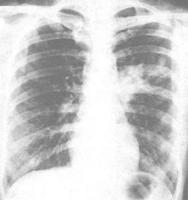

胸片?普通間質性肺炎肺炎是指終末氣道。肺泡和肺間質的炎症,可由疾病微生物、理化因素。免疫損傷、過敏及藥物所致。細菌性肺炎是最常見的肺炎。也是最常見的感染性疾病之一。日常所講的肺炎主要是指細菌性感染引起的肺炎,此肺炎也是最常見的一種。在抗生素套用以前,細菌性肺炎對兒童及老年人額健康威脅極大,抗生素的出現及發展曾一度使肺炎病死率明顯下降。但近年來,儘管套用強有力的抗生素和有效的疫苗,肺炎總的病死率不再降低。甚至有所上升。不是一個單一的疾病,而是一大類疾病的總稱,約有近百餘種,已知一小部分病因已明,如塵肺、藥物性肺炎肺炎是指終末氣道。肺泡和肺間質的炎症,可由疾病微生物、理化因素。免疫損傷、過敏及藥物所致。細菌性肺炎是最常見的肺炎。也是最常見的感染性疾病之一。日常所講的肺炎主要是指細菌性感染引起的肺炎,此肺炎也是最常見的一種。在抗生素套用以前,細菌性肺炎對兒童及老年人額健康威脅極大,抗生素的出現及發展曾一度使肺炎病死率明顯下降。但近年來,儘管套用強有力的抗生素和有效的疫苗,肺炎總的病死率不再降低。甚至有所上升。、放射性肺炎放射性肺炎(radiation pneumonitis)系由於肺癌、乳腺癌、食管癌、惡性淋巴瘤或胸部其他惡性腫瘤經放射治療後,在放射野內的正常肺組織受到損傷而引起的炎症反應。輕者無症狀,炎症可 ?自行消散;重者肺臟發生廣泛纖維化,導致呼吸功能損害,甚致呼吸衰竭。等;但也有部分病因不明,如特發性肺纖維化特發性肺纖維化(idiopathic pulmonary fibrosis,IPF)是一種原因不明、以瀰漫性肺泡炎和肺泡結構紊亂最終導致肺間質纖維化為特徵的疾病。按病程有急性、亞急性和慢性之分,所謂Hamman-Rich綜合徵屬急性型,臨床更多見的則是亞急性和慢性型。歐洲學者多稱本病為隱源性致纖維性肺泡炎(cryptogenic fibrosing alveolitis,CFA)。美國習用IPF。我國一度盛行CFA的名稱,近來卻多用IPF。本病多為散發,估計發病率3~5/10萬,占所有間質性肺病的65%左右。見於各年齡組,而作出診斷常在50~70歲之間,男女比例1.5~2∶1。預後不良,早期病例即使對激素治療有反應,生存期一般也僅有5年。、結節病結節病(Sarcoidosis)又稱肉樣瘤病,還有Boeck肉樣瘤Schaumann良性淋巴肉芽腫病和Besnier凍瘡樣狼瘡等名稱。為一種慢性肉芽腫病。堅實無破潰又無自覺症狀的皮膚損害外,還可侵入黏膜、淋巴結、骨骼及身體內部器官而稱全身性類肉瘤病。等。屬中醫“頑咳”之證。我們平時所說的間質性肺炎肺炎是指終末氣道。肺泡和肺間質的炎症,可由疾病微生物、理化因素。免疫損傷、過敏及藥物所致。細菌性肺炎是最常見的肺炎。也是最常見的感染性疾病之一。日常所講的肺炎主要是指細菌性感染引起的肺炎,此肺炎也是最常見的一種。在抗生素套用以前,細菌性肺炎對兒童及老年人額健康威脅極大,抗生素的出現及發展曾一度使肺炎病死率明顯下降。但近年來,儘管套用強有力的抗生素和有效的疫苗,肺炎總的病死率不再降低。甚至有所 ?上升。一般是指肺的間質組織發生炎症,炎症主要侵犯支氣管壁、肺泡壁,特別是支氣管周圍血管,周圍小葉間和肺泡間隔的結締組織,而且,多呈壞死性病變。中醫認為該病是由於脾腎不足,外邪客肺後,肺虛邪留,久則氣陰受損,肺臟脈絡瘀阻,宣肅失司,痰濁留戀肺竅,或陰虛津涸而致乾咳頻頻,成纏綿難愈的頑咳證。間質性肺炎肺炎是指終末氣道。肺泡和肺間質的炎症,可由疾病微生物、理化因素。免疫損傷、過敏及藥物所致。細菌性肺炎是最常見的肺炎。也是最常見的感染性疾病之一。日常所講的肺炎主要是指細菌性感染引起的肺炎,此肺炎也是最常見的一種。在抗生素套用以前,細菌性肺炎對兒童及老年人額健康威脅極大,抗生素的出現及發展曾一度使肺炎病死率明顯下降。但近年來,儘管套用強有力的抗生素和有效的疫苗,肺炎總的病死率不再降低。甚至有所上升。的最大特點是:起病隱襲、進行性加重、最終導致肺、心功能衰竭;因不易預防、不易早期發現、不好治療致進行性損害的不可逆的肺部損傷。 治療做效果最好的是中藥-溫腎清肺湯。

影像學特點

?胸部X線片主要表現是在兩肺基底部和周邊部的網狀陰影,常為雙側、不對稱性,伴有肺容積減少。CT對UIP的診斷具有重要的意義,主要表現為兩肺片狀、以基底部為主的網狀陰影,可有少量毛玻璃狀影。在纖維化嚴重的區域,常有牽引性支氣管和細支氣管擴張,和(或)胸膜下的蜂窩樣改變。